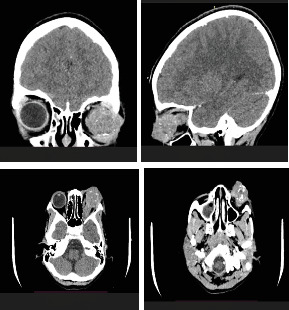

Objective: This report details the case of a 9-year-old Nigerian girl presenting with proptosis and a fungating ocular mass, which was histologically confirmed as retinoblastoma following exenteration. Introduction: Retinoblastoma is the most common pediatric intraocular malignancy, predominantly affecting infants and children under the age of 5, with leukocoria being the most frequent presenting symptom. The occurrence of retinoblastoma in older children is rare and often associated with atypical presentations. Case Summary: A 9-year-old Nigerian girl presented with a 1-year history of progressive left eye symptoms, including redness, pain, decreased vision, and proptosis. Examination revealed a large, fungating ocular mass with no light perception. Imaging studies (ultrasound B-scan and CT scan) confirmed extensive vitreous infiltration and optic nerve involvement. Histopathological analysis postmodified exenteration confirmed retinoblastoma. The patient clinically tolerated a modified exenteration and the first two of six planned cycles of systemic chemotherapy (vincristine, etoposide, and carboplatin). Unfortunately, she died during the second month of follow-up. The recurrence was characterized by progressive worsening of systemic symptoms and preauricular lymphadenopathy, likely indicating metastatic spread. Conclusion: This case highlights the aggressive progression of advanced retinoblastoma and the consequences of delayed presentation in resource-limited settings. Although the patient demonstrated an initial positive response, clinically tolerating modified exenteration and two cycles of systemic chemotherapy, she rapidly succumbed to the disease. This underscores the critical need for early diagnosis, prompt referral, and improved access to specialized care to enhance outcomes in similar contexts.